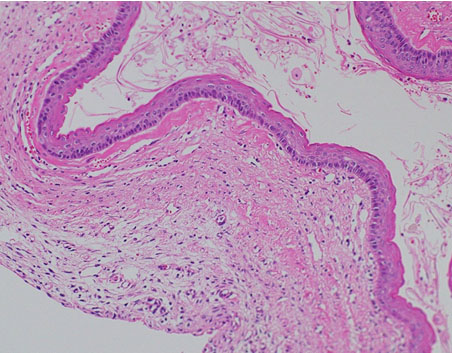

Histopathologically, the unilocular cyst was covered with thin and orthokeratinizing stratified squamous epithelium. Some parts showed mild erosion with neutrophilic infiltration in the epithelium. The cyst cavity was filled with a large amount of keratotic material, and hemorrhage, hyalinization, and mild infiltration of acute and chronic inflammatory cells were observed in the subepithelial stroma. Given the above findings, the final diagnosis was epidermal cyst.

Figure 6: Histopathological findings (hematoxylin-eosin staining, ×200). The unilocular cyst covered with a thin and orthokeratinizing stratified squamous epithelium. In some parts, mild erosion with neutrophilic infiltration in the epithelium is observed.